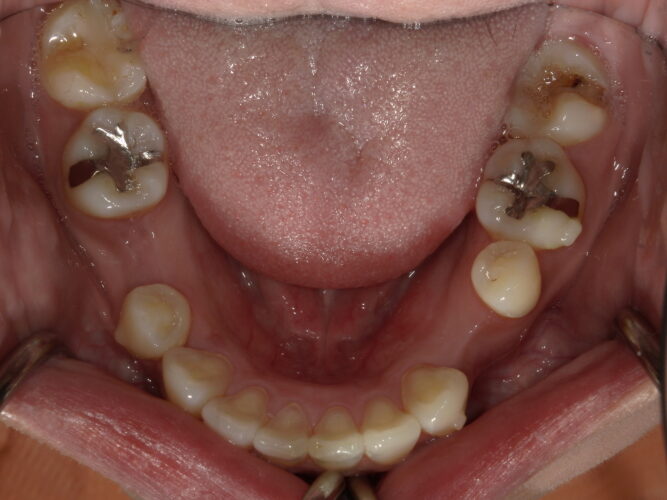

before

after

部分的な治療ではなく、咬合から全体的な調和を図ることで長持ちするインプラント治療が実現出来ます。

結果的に長期的なお口の中の安定と安心してなんでも噛める環境が実現できたと思います。